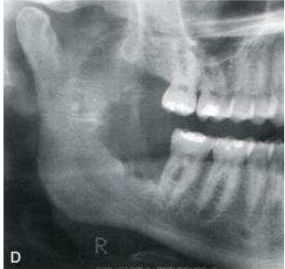

72. 下圖X光片中,右下第三大臼齒處和下顎上升枝所呈現之骨破壞,下列何種診斷最有可能?

(A)Ameloblastoma (B)Paget's disease (C)Fibrous dysplasia (D)Squamous cell carcinoma